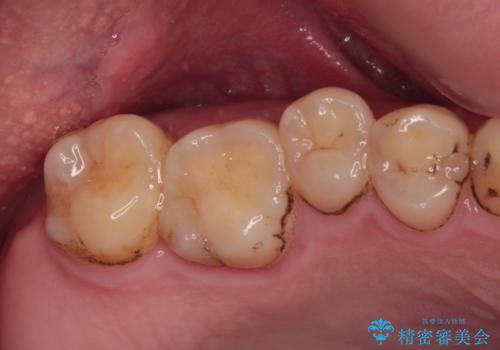

- 左下欠損部のインプラント治療を希望して来院された患者様です。

左下の欠損部を長期間欠損を放置していたことで、咬み合う上の奥歯が動いてしまっていたので、まずは上顎奥歯の部分矯正を行うこととしました。

理想的な咬み合わせに改善した上で、インプラント補綴治療を行うこととしました。